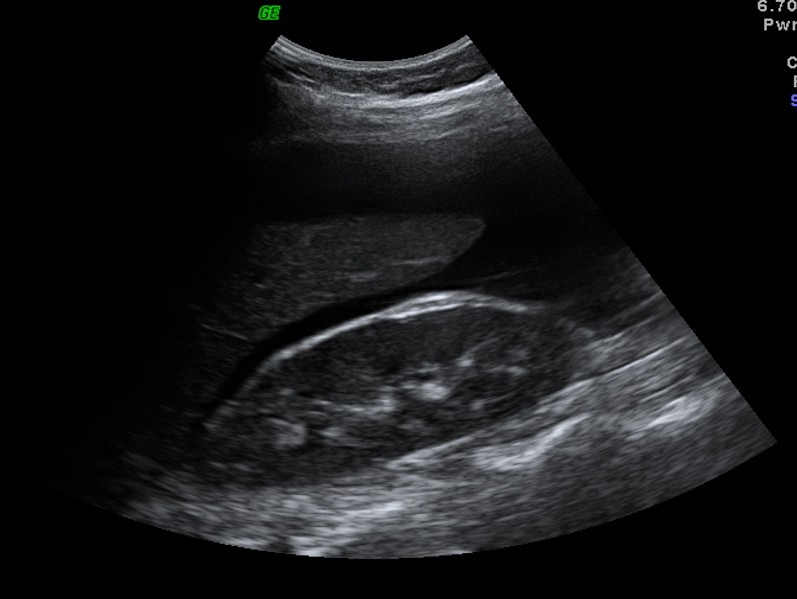

As regras simples do IOTA são um sistema de classificação baseado em características ultrassonográficas específicas que ajudam a distinguir massas anexiais benignas de malignas.

Classificação Benigna: Quando apenas regras benignas estão presentes (uma ou mais).

Classificação Maligna: Quando apenas regras malignas estão presentes (uma ou mais).

Classificação Indeterminada: Quando nenhuma regra está presente, ou quando há presença simultânea de regras benignas e malignas.